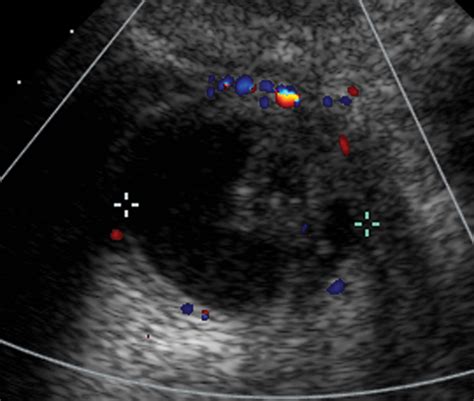

Diagnosis requires a high index of suspicion, especially when standard treatments for UTIs fail. A physician will typically perform a physical exam, which may reveal a tender mass along the anterior vaginal wall. If pressure is applied to the mass, it is not uncommon for a small amount of urine or purulent discharge to exit the urethra.

MRI (Magnetic Resonance Imaging) The gold standard for visualizing the size and location of the diverticulum.

Voiding Cystourethrogram (VCUG) Uses contrast dye to see if the pouch fills during urination.

Urethroscopy Direct visualization of the urethra using a thin camera to locate the diverticular opening.